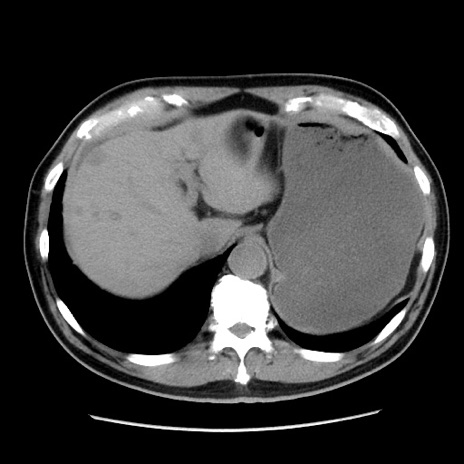

症例16(横断像)

【症例】 70歳代男性

【主訴】 腹痛、嘔吐

【現病歴】 約1ヶ月前より間欠的に腹痛と嘔吐あり、当院消化器内科を受診したところCTで多発する肝臓のLDAを指摘され、精査中であった。以降は消化器症状は安定していたが、2日前より嘔気と腹痛があり、同日より排便・排ガスが消失した。改善認めず、 本日、救急外来を受診した。

【既往歴】 大腸ポリープ切除後。

【身体所見】意識清明・会話良好、BT 36.3℃、BP 127/80mmHg、 P 80bpm、腹部:膨満あり、平坦・軟、上腹部正中および下腹部正中に圧痛あり、反跳痛なし、筋性防御なし。

【データ】WBC 7200、CRP 0.77